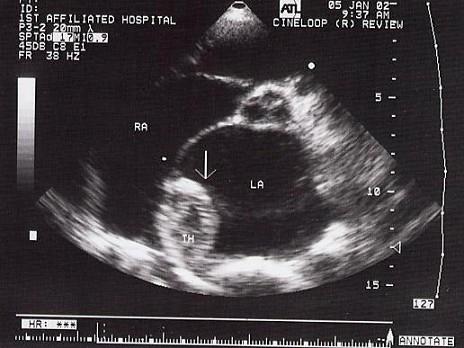

该病例最可能的诊断?(?)A.黏液瘤B.心房血栓C.心房云雾影D.房壁增厚E.赘生物

问题 该病例最可能的诊断?(?)

选项 A.黏液瘤 B.心房血栓 C.心房云雾影 D.房壁增厚 E.赘生物

答案 B